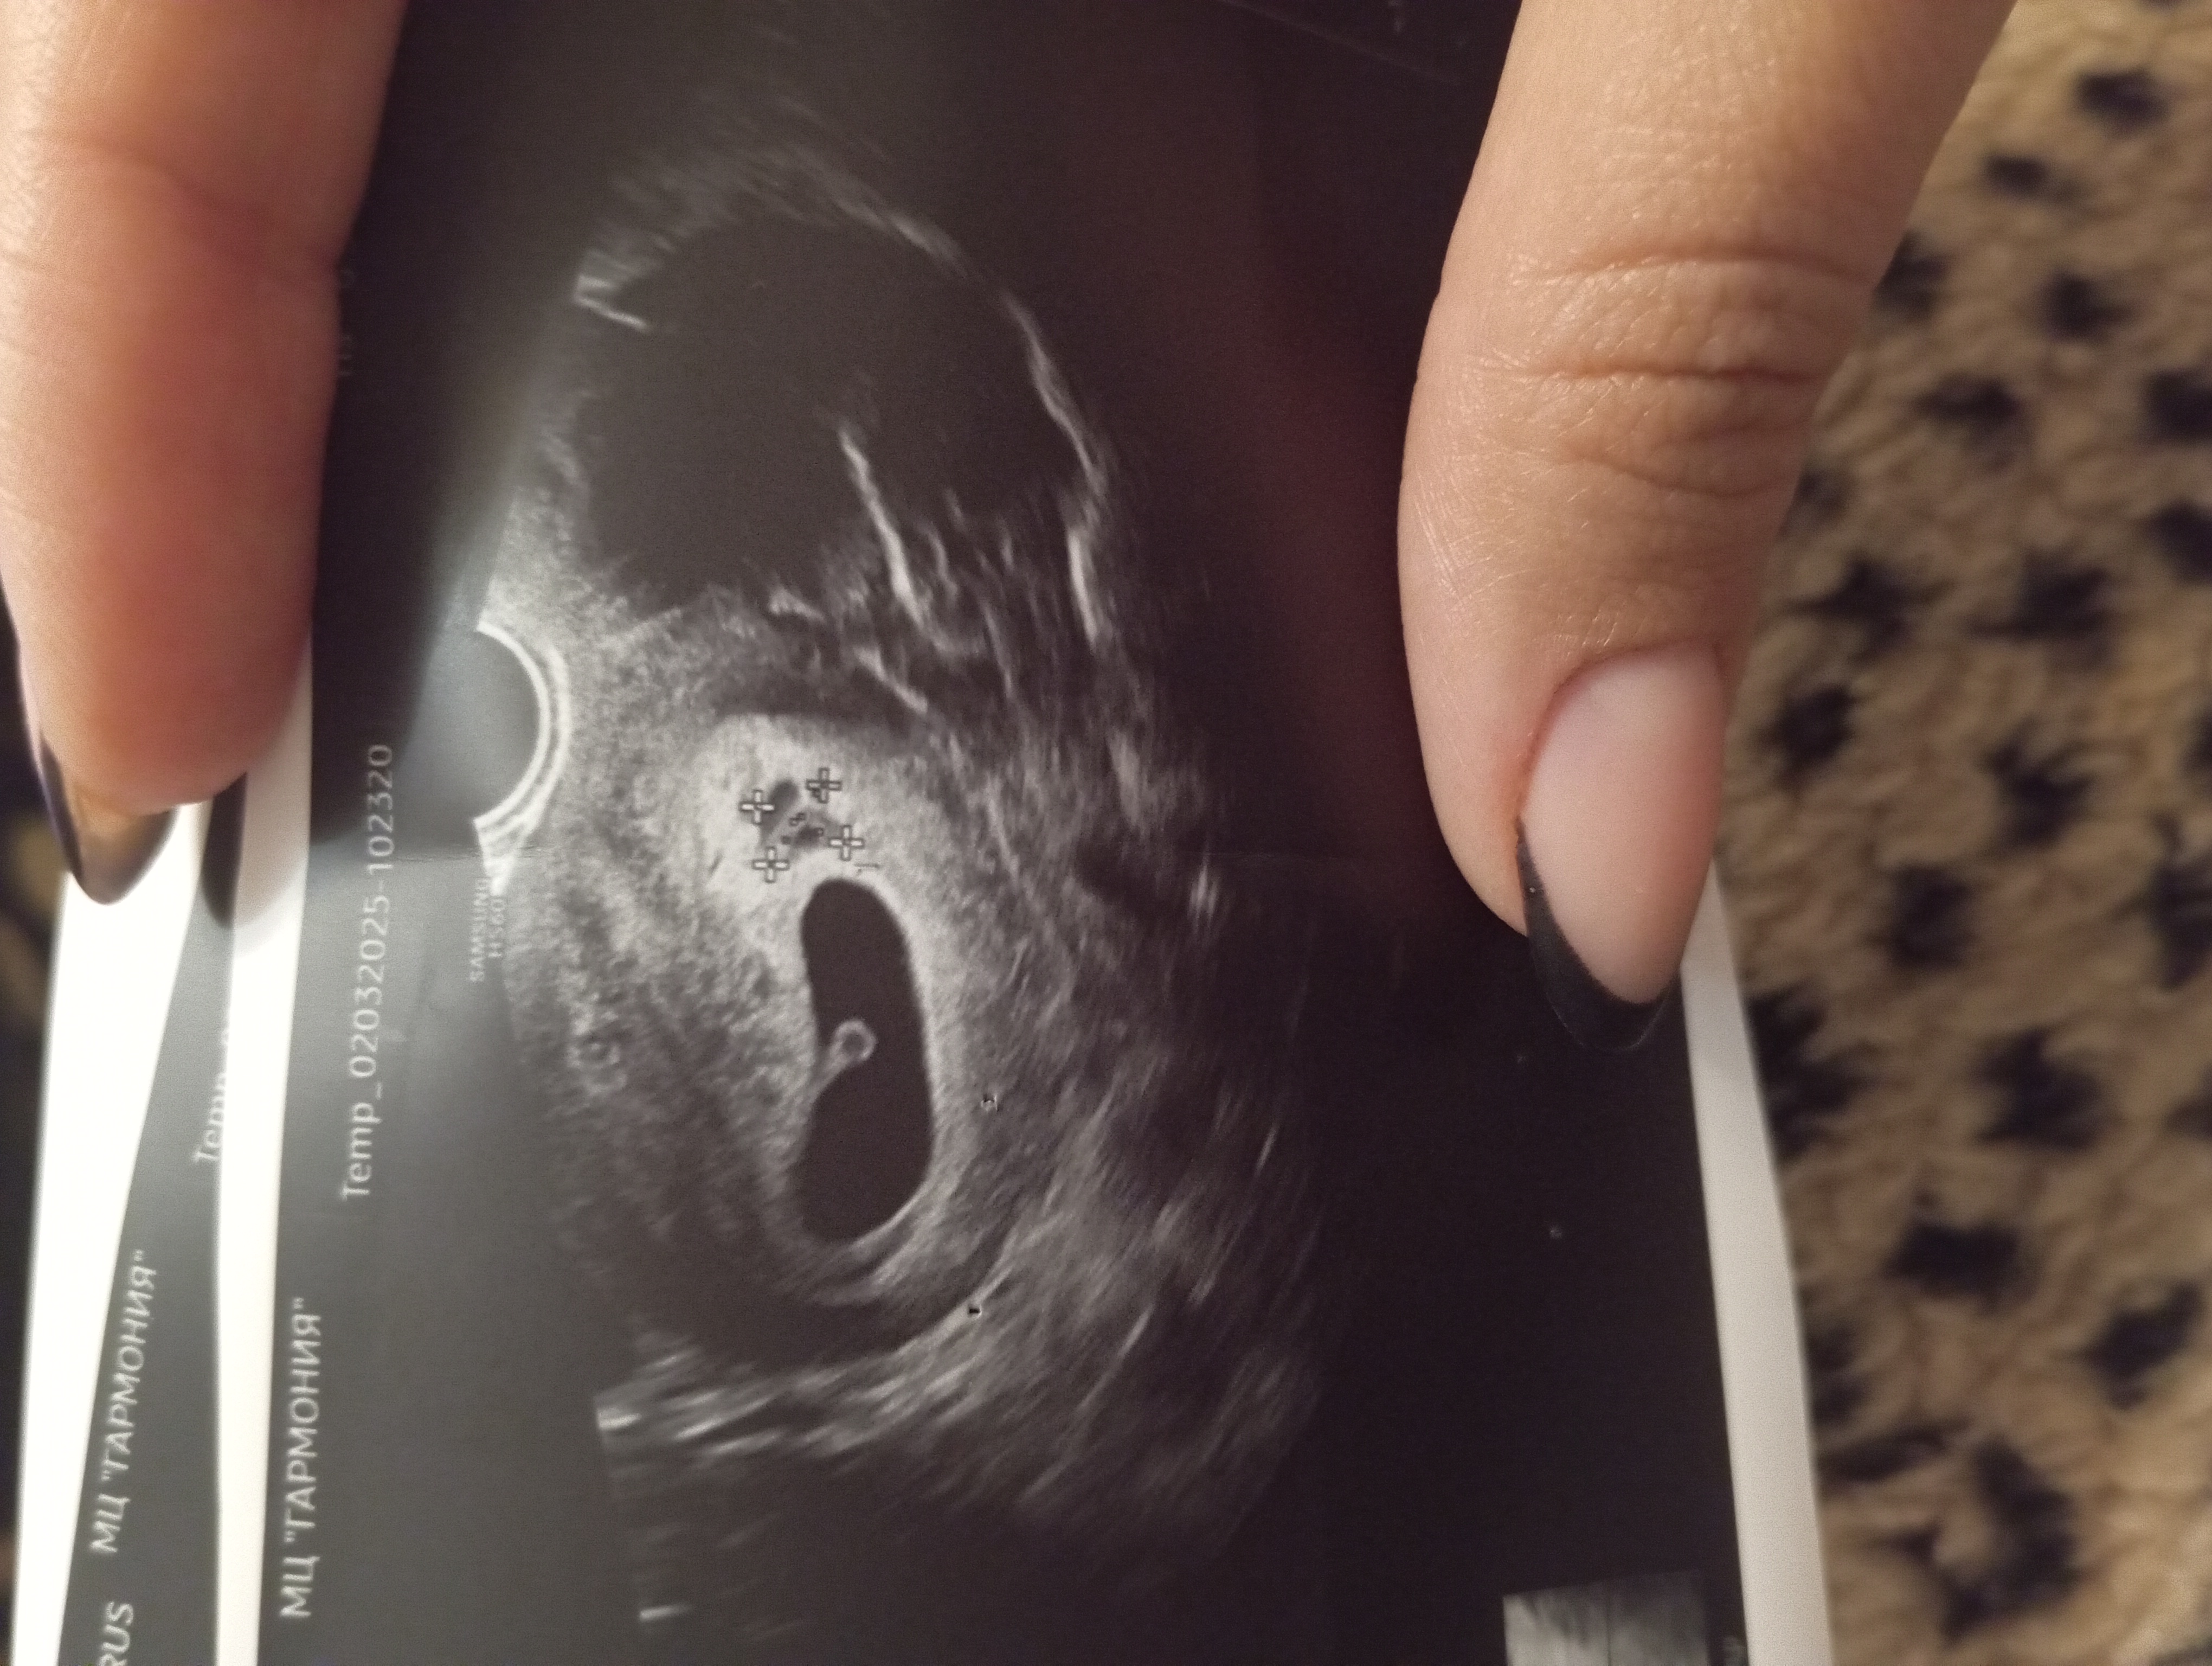

P.S Решила добавить фото отслойки, может так понятнее будет.

Результаты: УЗИ, КТГ, доплера, скринингаДевочки, вернулась сейчас с УЗИ: 6н 5д, по М 6н 6д. Ктр 7,4 мм, сб+. Киста уже левого (на УЗИ от 21.02 была правого) яичника 50х35мм.

Отслойка 10мм х 10мм. Идти завтра утром к гинекологу в поликлинику на дневной стационар, или ехать сразу в больницу ложиться? На сколько это опасно и серьезно? Алых и кровянистых выделений не было, единожды (в пятницу) на бумаге увидела молочно - бежевые выделения. Сейчас выделения молочно - прозрачные. Гематомы по УЗИ пока нет. Что предпринять?